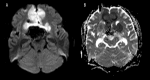

BACKGROUND Pituitary macroadenoma is a common benign tumor that usually presents with visual field defects or hormonal abnormalities. Cerebral infarction can be a complication of a large pituitary adenoma. We report a rare case of bilateral anterior cerebral arteries infarcts by a large pituitary macroadenoma with apoplexy. CASE REPORT A 48-year-old male patient presented with altered conscious level and sudden loss of vision for one-day duration. Magnetic resonance imaging of the brain showed a large seller and suprasellar hemorrhagic mass of pituitary origin, with associated bilateral areas of diffusion restriction in the frontal parasagittal regions, consistent with infarctions. Magnetic resonance angiography showed elevation and compression of A1 segment of both anterior cerebral arteries by the hemorrhagic pituitary macroadenoma. The patient underwent trans-sphenoidal resection of the pituitary adenoma, but unfortunately, ischemia was irreversible. Computed tomography (CT) done post-operatively showed hypodensity in the frontal and parietal parasagittal areas, which was also persistent in the follow up CT scans. The patient's neurological function remained poor, with GCS of 8/15, in vegetative state. CONCLUSIONS Vascular complications of the pituitary apoplexy, although uncommon, can be very severe and life threatening. Early detection of vascular compromise caused by hemorrhagic pituitary macroadenoma can prevent delay in intervention. Clinicians should also consider pituitary adenoma as a possible cause of stroke.